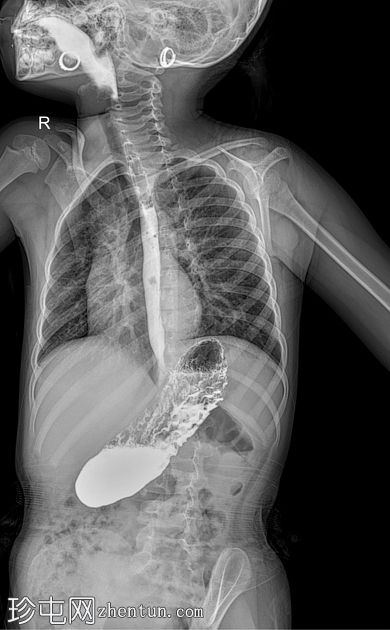

荧光透视

AP

斜向

食管体扩张,远端食管平滑收窄,呈现经典的鸟嘴状或鼠尾状外观

扩张食管内可见气液平面

造影剂进入胃排空延迟

荧光透视钡餐检查显示食管扩张,胃食管连接处平滑收窄,造影剂进入胃延迟。虽然这些特征提示贲门失弛缓症,但并非其特征性表现,尤其是在儿童中,因为下食管括约肌狭窄有时可视为正常变异。

贲门失弛缓症在儿科人群中并不常见,但对于年龄较大且存在非特异性上消化道症状的儿童,例如吞咽固体和液体食物困难、反流、体重下降或反复食物潴留,则应考虑该病。可能支持诊断的影像学征象包括:

食管均匀扩张

原发性蠕动消失

排空延迟

食管远端平滑收窄

荧光透视被认为是评估疑似贲门失弛缓症的一线影像学检查方法。